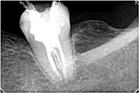

二.X光片:要求拍攝術前片、主尖片、根充完成片共三張牙片。

9.根管充填:要求根充物充填嚴(yan) 密,距x線片的根尖0.5—2.0mm。

五.完成牙體(ti) 修複:X線片顯示根管充填完好,行暫時或永久牙體(ti) 修複,視患牙狀況建議行全冠或樁冠修複。